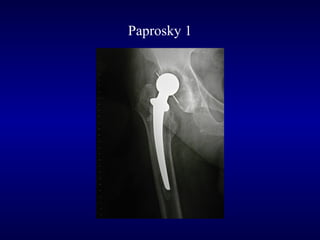

Paprosky 1

Post-op

F.U. 6 anni